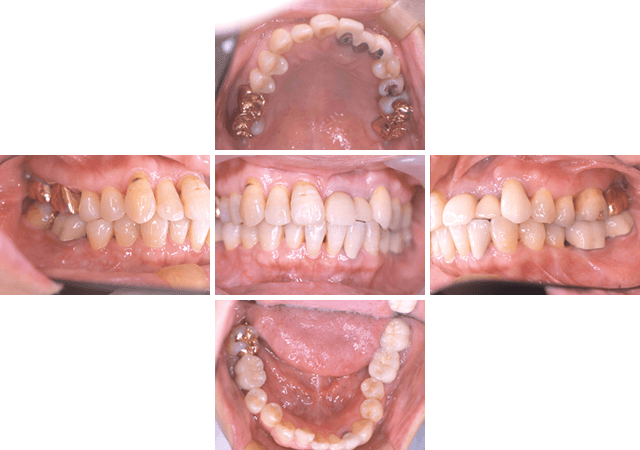

歯周治療の症例

比較的軽い歯周病であれば、歯や歯の周りを清潔に保つ治療を続けることで治すことができます。しかし、炎症が歯肉の奥まで進行し、歯周組織の破壊がひどい場合には、歯周組織を回復させるための手術 (歯周外科手術) が必要になります。この手術の際に、歯周組織再生誘導材料という手術治療を補助するための、歯科用の材料が使われることがあります。

エムドゲイン (歯槽骨の再生療法)

エムドゲインとは、スウェーデンの幼弱な豚の歯の芽から抽出したタンパク質です。歯が生えてくる時と同じ環境を作り出す事によって、再度、骨を歯の周囲に呼び込んで骨を再生させる作用があると言われています。(エムドゲインは厚生労働省承認の物質です)

当院でのエムドゲイン使用の歯周治療症例の一部を以下にご紹介します。